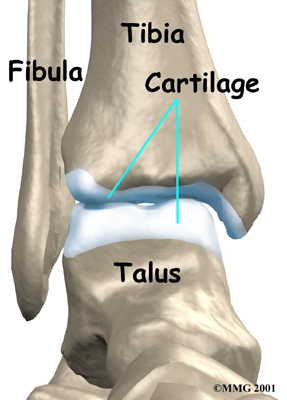

Inside the joint, the bones are covered with a slick material called articular cartilage. Articular cartilage is the material that allows the bones to move smoothly against one another in the joints of the body.

Articular Cartilage

The cartilage lining is about one-quarter of an inch thick in most joints that carry body weight, such as the ankle, hip, or knee. It is soft enough to allow for shock absorption but tough enough to last a lifetime, as long as it is not injured.